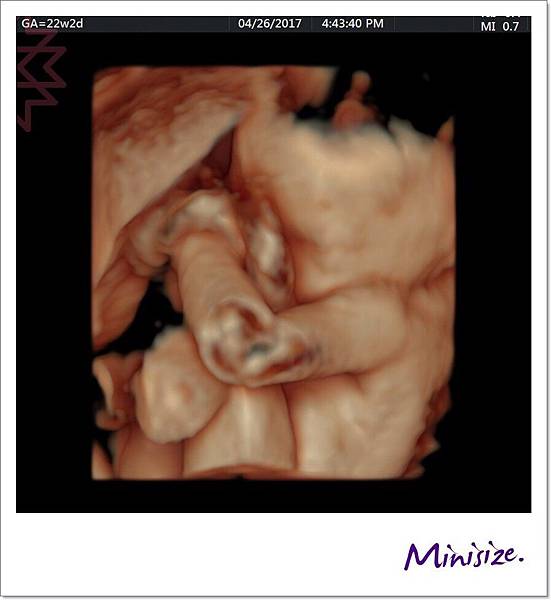

手

剛好我的寶寶手手有摺起來

技術師用兩種不同角度拍照

檢查時會細數1、2、3、4、5 五支手指頭

下兩張左圖都是大拇指 右圖是其餘四指

手指看起來很修長應該是遺傳麻麻

性別

一樣是男生

小雞雞實在是清楚呀!